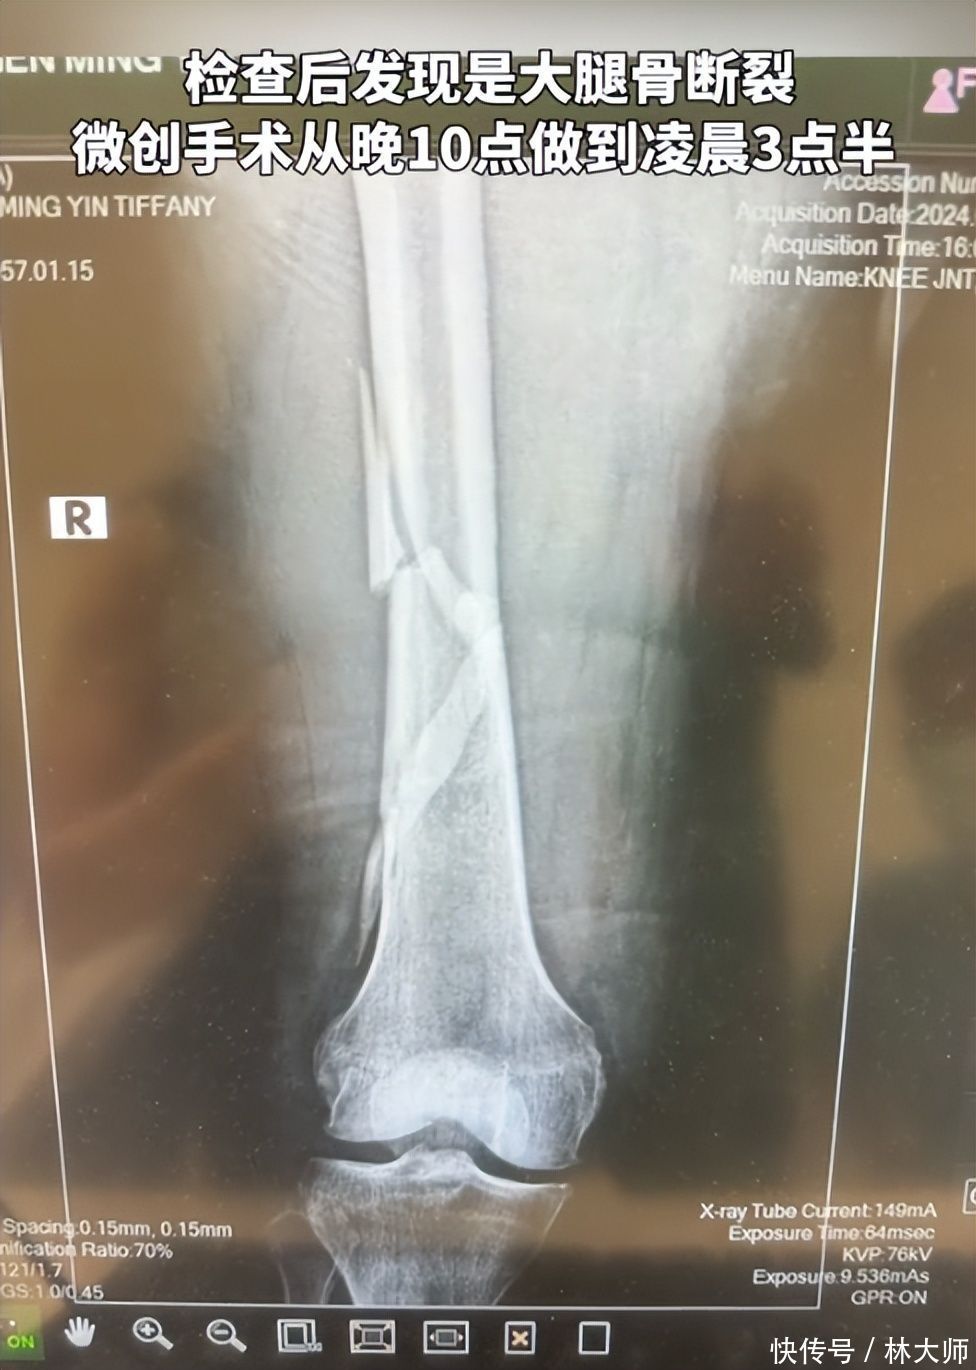

4月26日,向太晒出我方近期颠仆骨折的阅历。她在着迷间着迷时,在莫得防滑垫的地点重重颠仆,就地大腿骨断裂,痛到怀疑东谈主生。

第二天私东谈主医师来家里,把向太固定在担架上,送到了病院。向太的大腿骨断裂很严重,仍是严重错位,需要立即手术,而因为伤势严重,手术足足进行了5个半小时。向太的大腿受骗今全是钢钉,伤筋动骨一百天,这些钢钉需要好几个月智商破除。